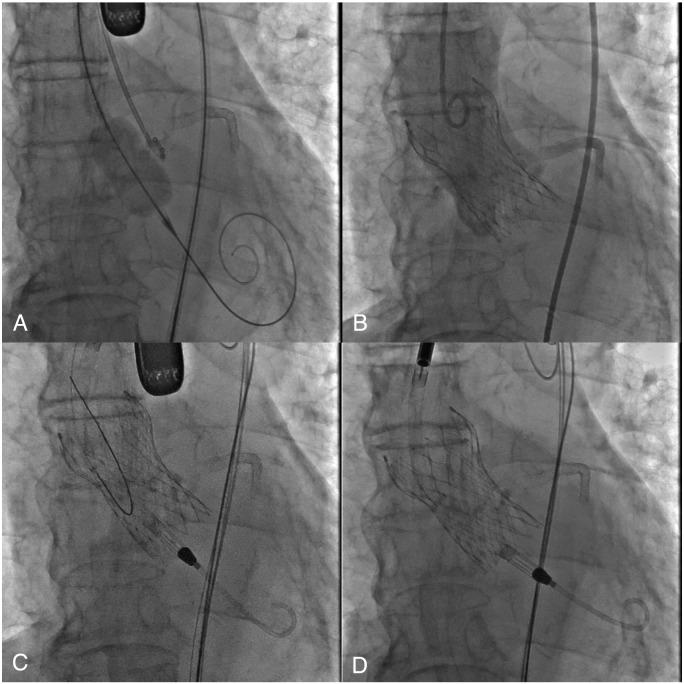

An 84-year-old man with chest pain was transferred to our institute and subsequently diagnosed with ST-elevation myocardial infarction and Killip class III heart failure. The patient was intubated, and urgent coronary angiography revealed severe tandem stenosis from the proximal to mid-left anterior descending coronary artery. We performed a primary percutaneous coronary intervention (PCI) and deployed drug-eluting stents from the left main trunk to mid-left anterior descending coronary artery. Although the procedure was successful, the patient went into cardiogenic shock a few hours later. Transthoracic echocardiography revealed low cardiac function and severe aortic stenosis. We decided to perform transcatheter aortic valve implantation using a self-expandable valve, followed by the insertion of a left ventricular assist device. The combination of procedures achieved haemodynamic stability.

It is difficult to treat cardiogenic shock that develops in patients with severe aortic stenosis and ST-elevation myocardial infarction. This case report demonstrates that combined transcatheter aortic valve replacement using a self-expanding valve and left ventricular assist device placement can be safe and effective after a primary PCI.